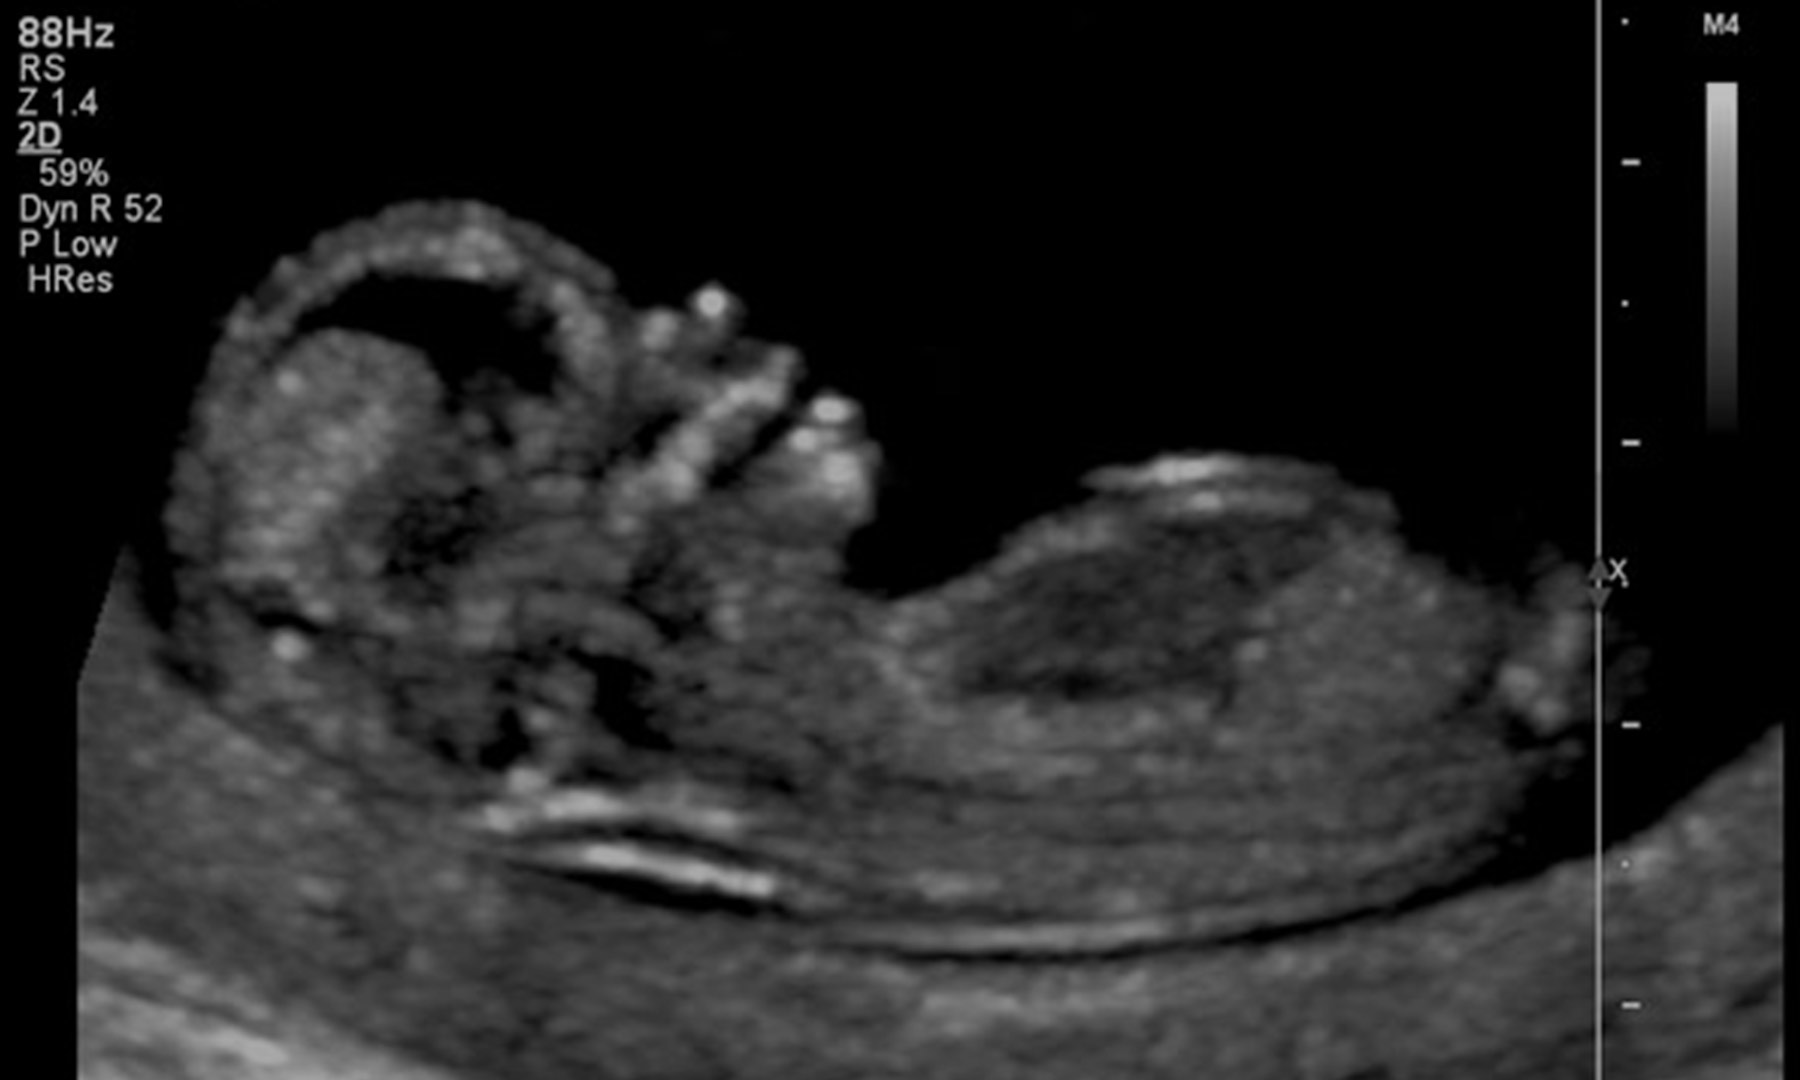

Designed to meet the evolving demands of modern healthcare, the program emphasizes diagnostic imaging, critical thinking, professionalism, and clinical competency across abdominal, obstetrical/gynecological, and related sonographic specialties. Students complete comprehensive didactic coursework, specialty-focused sonography education, and extensive supervised clinical experience to ensure graduates are workforce-ready and prepared for professional credentialing.

Diagnostic medical sonography is a non-invasive imaging profession that uses high-frequency sound waves (ultrasound) to produce dynamic visual images of organs, tissues, and blood flow within the body. Sonographers play a vital role in patient diagnosis, care, and interdisciplinary healthcare collaboration.